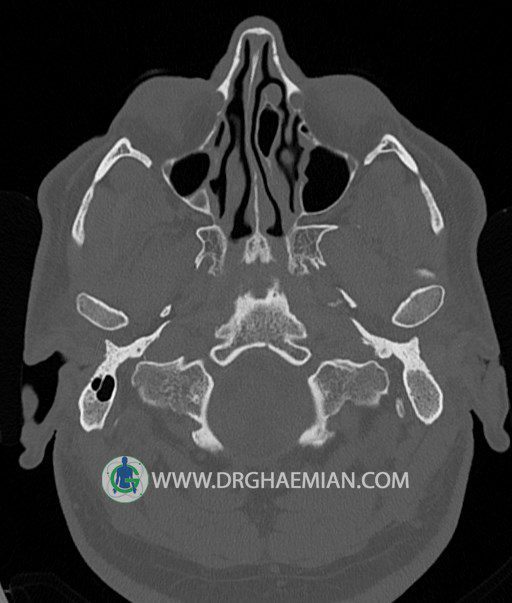

سی تی اسکن گوش داخلی به رادیولوژیست اجازه می دهد تا سطوح مختلف، یا اسلایس هایی از استخوان های که از جمجه به گوش می روند را از طریق امواج ایکس چرخشی مشاهده کند. در این کیس اودیت مدیا، ماستوئیدیت مزمن، اوتیت خارجی، انحراف سپتوم بینی، کونکا بولوزا و افزایش ضخامت سینوس ها مشاهده می شود.

گزارش پزشک :

در HRCT از استخوان تمپورال با مقاطع آگزيال ، ساژيتال و کرونال ظريف ( 0.6 mm ) :

– نماي کوکلهآي دو طرف با 2.5 دور گردش مجرا

– نماي cochlear aqueduct

– نماي semicircular canal خلفي ، لترال ، فوقاني و وستيبول

– استخوانچه هاي گوش داخلي شامل malleus ، incus و stapes (دنسيتي و رديف استخوانچه ها )

– نماي oval window و round window ، tympanic cavity ، attic و کانال گوش داخلي

– کانال عصب فاشيال و مسير ان از ناحيه کانال گوش داخلي ، geniculate ganglion تا محل خروج ان از stylomastoid foramen

– نماي tympanic membrane ، کانال ICA ، بولب جوگولار دو طرف

در حد طبيعي است .

– اپاسيتي گوش مياني چپ ناشي از وجود دانسيته نسج نرمي دراطراف استخوانچه ها همراه با اروژن اسکوتوم و

استخوانچه ها بدون جابجايي در رديف استخوانچه ها مشهود است که مطرح کننده اوتيت مديا همراه با نشانه

هاي مشکوک به کولستئاتوم مي باشد .

– اپاسيتي و اسکلروزيس ماستوئيد چپ نشانه ماستوئيديت مزمن

– اپاسيتي کانال گوش خارجي ناشي از دانسيتي نسج نرمي مطرح کننده external otitis

– انحراف سپتوم مياني بيني به راست

– کونکا بولوزا در کونکاي مياني چپ و

– افزايش ضخامت مخاطي در سينوس هاي اتموئيد و ماگزيلاري

اپاسيته